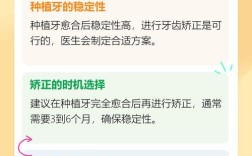

Q2:植骨后要等多久才能种牙?

A:一般植骨后需3-6个月等待新骨形成(自体骨愈合快,人工骨稍慢),具体时间取决于骨缺损大小、患者年龄和骨愈合能力。